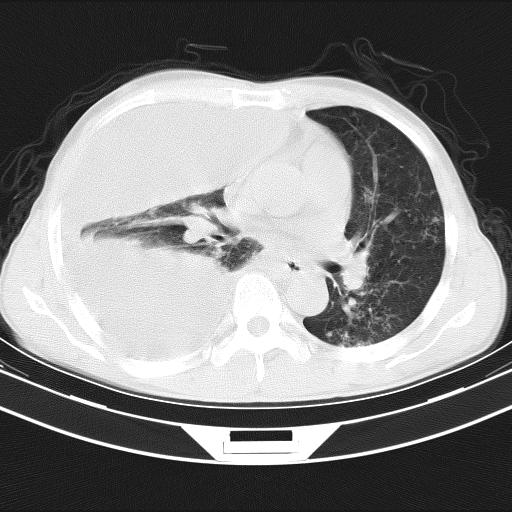

男性,44岁,结核病史多年。现胸闷气短,咳嗽,偶咳血。

右侧胸腔积液

右肺下叶不张

双肺多发结节影最分空洞形成考虑占位不除外结核

双肺陈旧性病变

1、右侧大量胸腔积液伴右肺压缩性膨胀不全,建议抽液治疗后复查 2、两肺继发性tb伴空洞形成。

1)两肺继发性肺结核伴空洞形成,左肺多发性结核球。2)右侧大量胸腔积液伴右肺部分膨胀不全。3)纵隔淋巴结肿大。

1,双肺多发结节 并空洞影改变, 左侧胸腔积液并部分包裹, 结合原病史首先考虑结核. 但也不除外其它.

2,左侧有一根肋骨陈旧性骨折? 建议追查 .